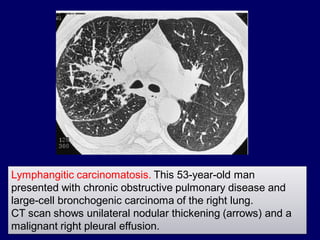

Lymphangitic carcinomatosis. This 53-year-old man

CT scan shows unilateral nodular thickening (arrows) and a

malignant right pleural effusion.